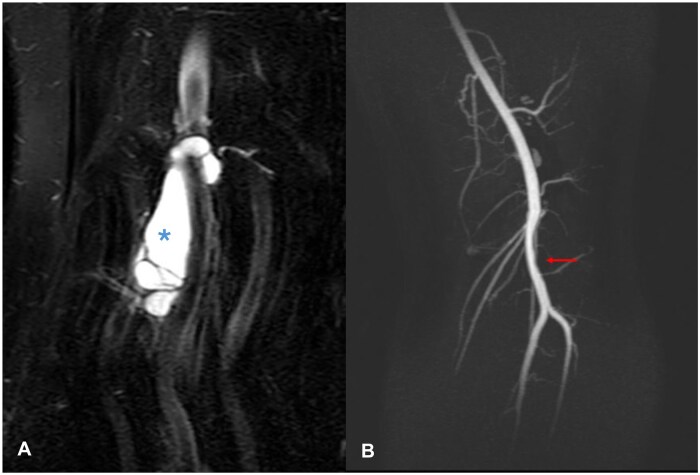

囊性外膜病是一种罕见的小腿跛行原因,其特征是在动脉外层(外膜)内发生粘液囊性肿块。腘动脉最常受影响。关于这种疾病的病因存在几种理论和假设,迄今为止文献中没有明确的统一原因。我们描述了一个32岁的女性病例,她有一年的右膝内侧疼痛和间歇性跛行史,她被诊断为内侧半月板撕裂和一个与腘动脉外膜相连的大腹膜旁囊肿。她接受了关节镜半月板切除术和囊肿减压,并获得了良好的功能结果,跛行得到了解决。

Cystic adventitial disease is a rare cause of calf claudication and is characterized by the development of a mucinous, cystic mass within the outer layer (adventitia) of an artery. The popliteal artery is most commonly affected. Several theories and hypotheses exist regarding the aetiology of this disorder with no clear unifying cause accepted in the literature to date. We describe a case of a 32-year-old female with a one-year history of medial right knee pain and intermittent claudication who was diagnosed with a medial meniscal tear and a large parameniscal cyst communicating with the popliteal artery adventitia. She underwent arthroscopic meniscectomy and cyst decompression and achieved an excellent functional outcome with resolution of the claudication.